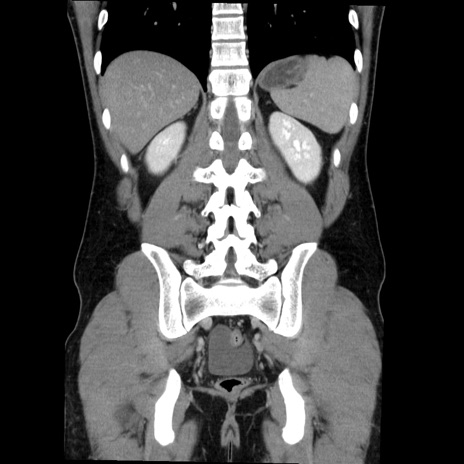

症例36(冠状断像)

【症例】20歳代 男性

【主訴】心窩部痛

【現病歴】今朝より上腹部痛あり。一旦軽快していたが再度出現したため救急要請。昨日夕に白身の魚を含む刺身を食べた。

【身体所見】BP 136/89mmHg、HR 74/min、BT 37.0℃、腹部:膨満、軟、心窩部に圧痛あり。反跳痛なし、筋性防御なし、腸雑音やや亢進あり。

【データ】WBC 17700、CRP 0.48